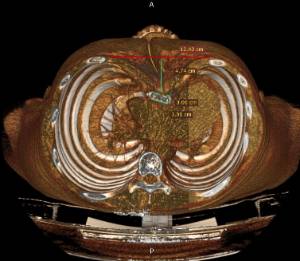

Los datos médicos del paciente, más la exploración clínica realizada por el equipo de cirugía, junto a un análisis pormenorizado de las imágenes del TAC y las reconstrucciones digitales en 3D de cada tórax realizadas conjuntamente con el equipo de ingenieros de Ventura Medical Technologies, son la base para determinar si la técnica Pectus Up está indicada y como se debe proceder en cada uno de los pacientes.

Con estos datos se selecciona el implante que mejor se ajustar a la anatomía de cada tórax, la ubicación exacta del sistema de elevación y, a su vez, proporciona al equipo quirúrgico un detalle de los pasos a tener en cuenta para llevar a cabo una correcta implantación.

Pectus Excavatum Pectus Excavatum Asimétrico Índice de Asimetría 0.6 (+R/-L)(|AI|> 0.05 Asimétrico) Índice de Haller 4.5 (HI >3.5) Índice de Corrección 49.13% Rotación esternal 18.1 ° (a la derecha)

Informe de evaluación del TAC de un paciente enviada al cirujano